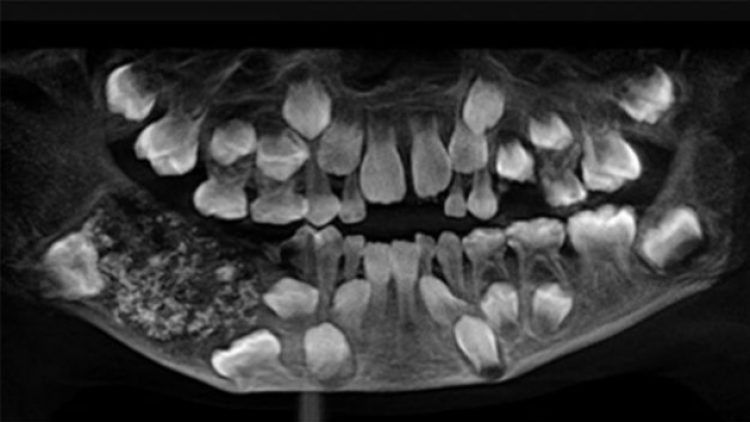

Hindistan’ın Cennai şehrinde 7 yaşındaki çocuğun ağzından boyutları 1 milimetre ile 15 milimetre arasında değişen tam 526 adet diş çıkarıldı.

Bu sert yapı kesilerek açıldığında daha önce görülmemiş, boyutları 1 mm’den 15 mm’e kadar değişen 526 adet diş benzeri parça bulundu. Doktorlara göre her biri diş minesiyle kaplıydı ve kök yapısına sahipti.

Saveetha Diş Üniversitesinden Prof. Dr. Senthilnathan, “Genel anestezi uyguladıktan sonra çeneyi açtık ve içeride çanta/çuval gördük. Yaklaşık 200 gram ağırlığındaki çuval dikkatle çıkarıldı ve daha sonra içinde küçük, orta, büyük 526 diş olduğu fark edildi” dedi.

Geçirdiği son operasyonun ardından çocuğa diş gelişimiyle ilgili iyi huylu bir tümör olan “karışık odontoma” teşhisi kondu. Çocuk diğer 21 normal dişini koruyabildi ve ameliyatı ücretsiz gerçekleştirildi.